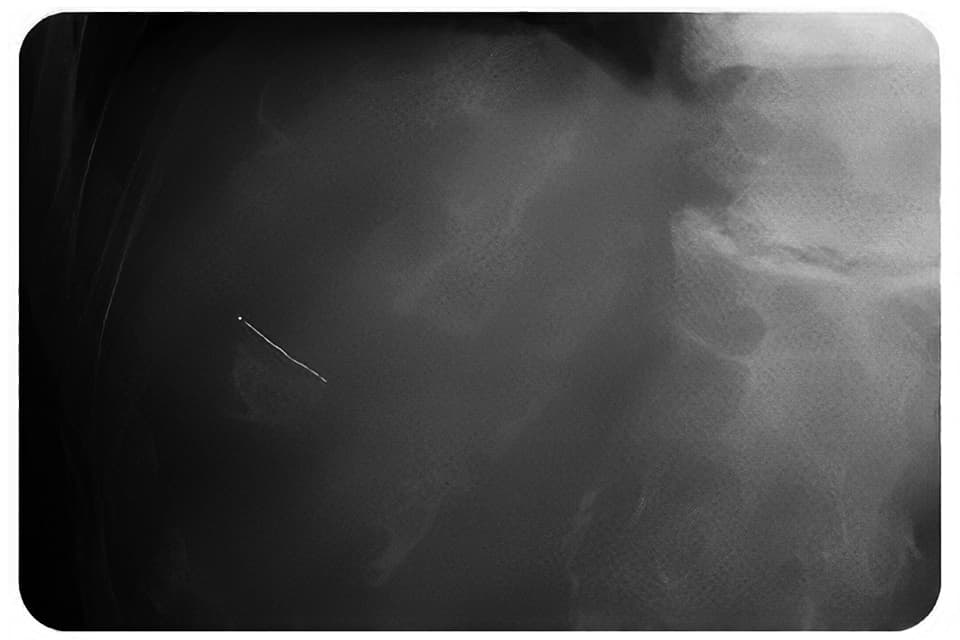

KeV-X線

各種画像診断モダリティ(CT、CBCT、kV-X線、MRI、超音波)での明瞭な可視性があります。

Gold Anchorマーカの特徴-3 優れた可視性

Gold AnchorマーカはMRI装置における可視性の向上をはかるため、99.5%の金と0.5%の鉄の合金としています。